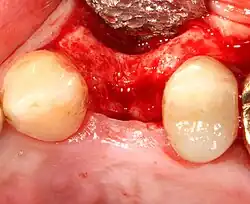

An incision is made across the area and the flap of gingiva is opened to show the bone of the jaw.

An incision is made across the gingiva, and the flap of tissue is reflected to show the bone of the jaw.